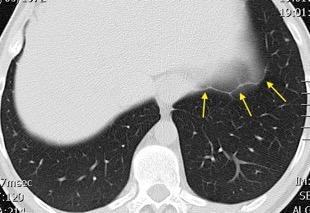

Síndrome antisintetasa

(Miositis anti Jo-1).

Artralgias migratorias, Miositis, “Manos de mecánico”, Raynaud y Enfermedad

intersticial pulmonar (>70%).

Waseda Y et al.. Eur J Radiol. 2016